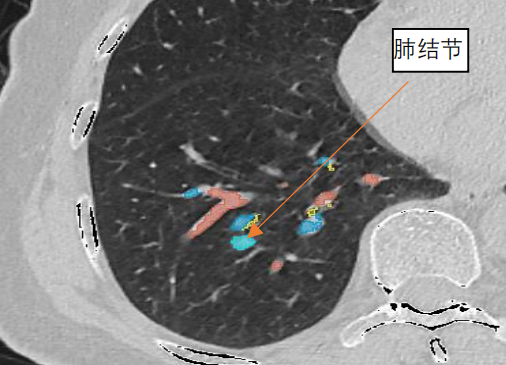

随着大众对健康的重视,肺CT扫描筛查的人群越来越多,许多的肺小结节被发现。CT发现有肺小结节后患者往往非常恐慌,那么如果发现有肺小结节究竟该怎么办? 临床上将CT检查显示的肺部直径小于 30mm的类圆形或者不规则密度增高阴影称为肺结节。而如果直径小于20mm习惯上称肺小结节,直径小于5mm,称微小结节。CT显示结节有的密度很高或者有钙化,有的显示为纯磨玻璃样阴影,有的则显示为混杂磨玻璃样结节。 当发现肺上有结节之后,自然想知道肺结节是良性还是恶性,下一步就是怎么治疗。患者可能会去很多医院就诊,网上搜索相关知识,得到的回答可能各不相同。有的认为肺结节是肺癌可能性很小,建议观察随访。有的建议手术,有的建议穿刺检查。患者究竟该听取那个医生的建议呢?这是一个很复杂的问题,既然医生给出不同建议、没有确定方案,就说明有很多问题需要进一步研究。 最具权威性的NCCN指南推荐:直径 8mm以下观察,8mm以上可以考虑手术。但肺结节的诊疗方案真的就如指南这样简单吗?肺小结节的诊断及治疗牵涉很多因素,手术能够完全治愈肺癌。如果肺小结节是肺癌,肯定越早手术越好,因此肺小结节患者的选择其实就是随访观察或者手术。 那也有患者会问,手术前可不可以穿刺明确诊断呢? 穿刺有两种结果,找到癌细胞和没找到。但如果没找到,也不能排除是肺癌的可能,还是需要手术;找到了,那肯定更需要手术,所以穿刺对需要手术的患者,没有价值。相反,穿刺肯定会刺破肿瘤的基膜,可能造成癌细胞种植、血液及淋巴结管播散,让本来是早期的肺癌变成晚期。 虽然有文章报道肺小结节是肺癌的可能性很小,但是在我们医院经我们会诊后手术的肺小结节患者,90%都是肺癌。因此发现肺部结节千万不能大意,一定要去正规的三甲医院,尤其是肿瘤医院的胸外科就诊,听取专家意见。 究竟是观察或者手术,以下因素需要综合考虑。 CT提示结节较大,直径超过8mm,即使高度怀疑肺癌的结节,最少还是可以观察2周时间,看结节会不会缩小或者消失,然后才考虑是否需要手术。 如果结节很小,直径小于5mm,大部分都可以长期随访观察,除非结节形态高度怀疑肺癌,经随访结节持续存在,甚至有微小变化,可以考虑手术切除。 如果CT发现增值病灶或者有钙化灶,一般会建议随访,考虑良性可能性大。这种情况建议每年复查CT就可以。 纯磨玻璃结节直径小的可以随访,半年或者一年随访一次胸部CT。较大的考虑原位腺癌,原位癌不会发生转移,所以随访时间长也不用太担心。 混杂样磨玻璃结节尤其是实性成分占多数的,这种情况肺癌可能性显著增加, 而且会有癌细胞侵润,不适合长时间随访,应该尽早手术,即使结节直径小于8mm。 结节的位置对于制定诊疗计划也很重要。左右各侧肺分为上肺叶、中(舌肺叶)及下肺叶。每个肺叶又由很多肺段组成。 建议长期观察随访的肺结节,我们会根据病灶位置及大小形态来建议观察随访间隔时间长短。如果结节靠近肺门,考虑肺癌可能,会建议密切观察,3个月做一次CT。因为靠近肺门的结节,一旦增大,手术切除就比较困难,而且容易发生肺门淋巴结转移。随访间隔时间长,肿瘤增大较快,由于靠近肺门,可能造成肿块边缘距离正常组织的切缘不够,肿瘤容易复发甚至不能完全切除。 靠近肺周边的结节,尤其是靠近胸膜的肺结节,经过一段时间随访,如果结节形态像肺癌,可以积极手术切除。理由是: 1.靠近胸膜结节容易转移,胸膜种植; 2.对周边肺结节切除肺组织相对少,对患者肺功能影响很小。 图1 肺结节位于肺实质较深的位置 如果肺结节位于肺实质较深的位置(图 1),但在肺段的中间,可以行肺段切除,这种情况也可以相对积极手术。但是如果结节位置较深,同时位于几个段交界处,又不适合亚肺段切除,则可以继续观察,在结节继续增大或者出现部分实性成分,再考虑肺叶切除。 肺功能也是制定手术方案时需要考虑的因素。有的患者肺功能较差,只能承受肺段或者楔形切除手术,甚至不能手术,这种情况我们在确诊后可以考虑射频消融及术后辅助治疗。对于多个肺结节,需要切除较多肺组织,而肺功能不容许,可以切除部分表浅的肺结节,对深部的结节射频消融。这部分患者术后需要化疗及靶向治疗。 胸腔镜手术应用已经很普及了,手术创伤小,患者恢复快。我们开展的单孔腔镜手术(图2),创伤更小,一个3cm 小孔,可以完成肺部各种手术。如果没有掌握单孔腔镜技术,尤其是有的医生甚至还要开胸撑开肋骨创伤较大的手术方式,对肺结节的手术,可以更保守一点,随访时间更长,确诊后再手术。 图2 单孔腔镜手术 肺结节的治疗,医院设备条件也是非常重要。除了手术设备,更重要的是肺结节定位设备。由于我们开展的单孔腔镜手术,对磨玻璃结节用指头去触摸很困难,而且不准确。有的部位手指到达不,因此就需要一些设备方法在手术前及手术中对肺结节的精确定位。 图3 三维成像技术 三维成像技术(图3)在临床中使用最广,因为对设备需要不高,只要一台电脑,下载mimics软件,就能对肺结节定位和规划手术。这其实就是将薄层CT 图像整合成三维图形,便于更直观的观察解剖位置及与支气管及血管的关系。但是这种技术定位肺结节有很大局限性。CT是在肺膨胀时候采集的图形,因此做出的三维图像是肺膨胀时的图像,而我们在手术中肺是萎陷的,肺缩小很多,和膨胀时差别很大。如果肺结节刚好在段的中间位置,做肺段切除借助三维成像很有帮助。但是如果结节在几个段交界或者靠近段边缘,手术有可能漏掉结节,或者把结节切碎,导致肺癌复发。 目前更先进的设备有肺结节导航系统,包括磁导航和更先进LUNG-pro导航技术(图4)。可以对肺深部的结节定位,注射染色剂或者放置标记物定位。 图4 肺结节导航系统 手术室中的移动CT(图5),可以让手术变得更简单。重庆大学附属肿瘤医院复合手术室配备有移动CT,患者麻醉之后摆好手术体位再用定位针定位,患者处于麻醉状态,定位更准确,患者没有恐惧感觉,而且没有风险。 图5 重庆大学附属肿瘤医院复合手术室中的移动CT 手术切除肺段时需要判断肺段间的界面,大多数医院都是采用膨胀萎陷法。不过由于有的患者有肺气肿,手术中肺萎陷不好,这种方法就不适用。重庆大学附属肿瘤医院的荧光腔镜(图7)可以精确定位肺段界面,当相应的肺段动脉切断后,静脉注射吲哚青绿,要切除的肺段就不会显示染色。这种方法准确,也缩短了手术时间,又能最精确手术。 肺小结节是观察还是手术,不是只看大小及有无实性成分,更要根据每个患者的个体情况,考虑到各种因素,力求个体化的治疗方案。为了达到精准治疗肺小结节,重庆大学附属肿瘤医院胸部肿瘤中心全科室医生均采用单孔的肺结节手术,中心配备了全球最先进的设备,综合实力全球领先。时刻为了患者的健康保驾护航。